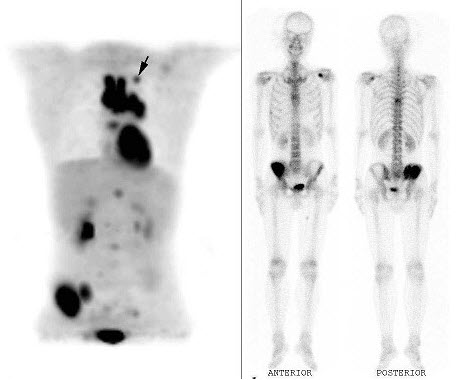

59、多项选择题

一患者的心肌灌注显像对比如图,正确的诊断是()

A.左心室前壁可逆性缺血

B.PTCA疗效显著

C.PTCA无明显疗效

D.术后再狭窄

E.以上都不是